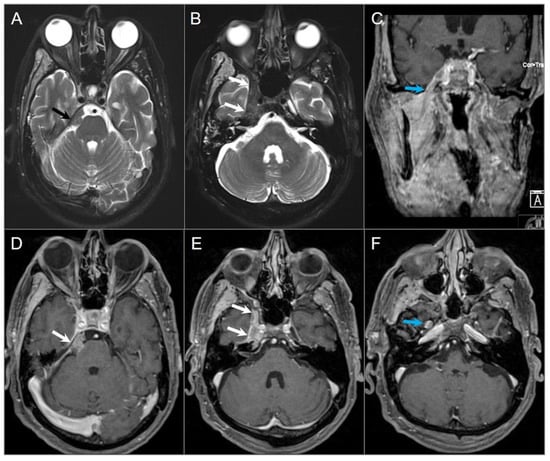

4.4.5. Paraganglioma

5.11. Giant Aneurysm